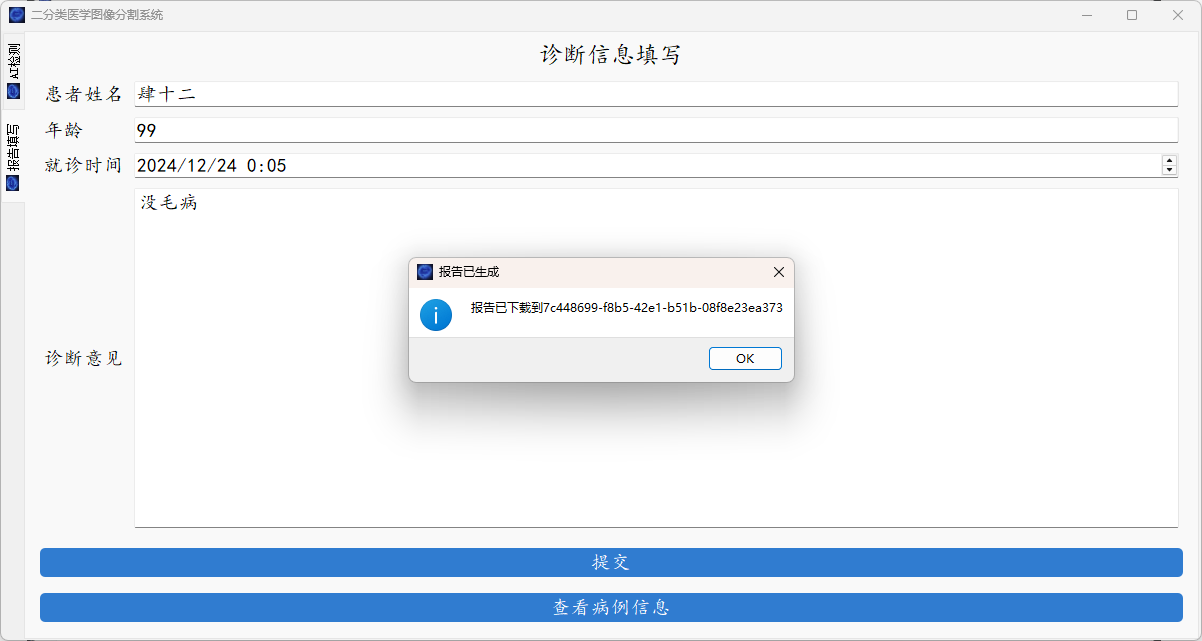

系统支持医学图像的分割、轮廓的查找以及简单的病例的记录。